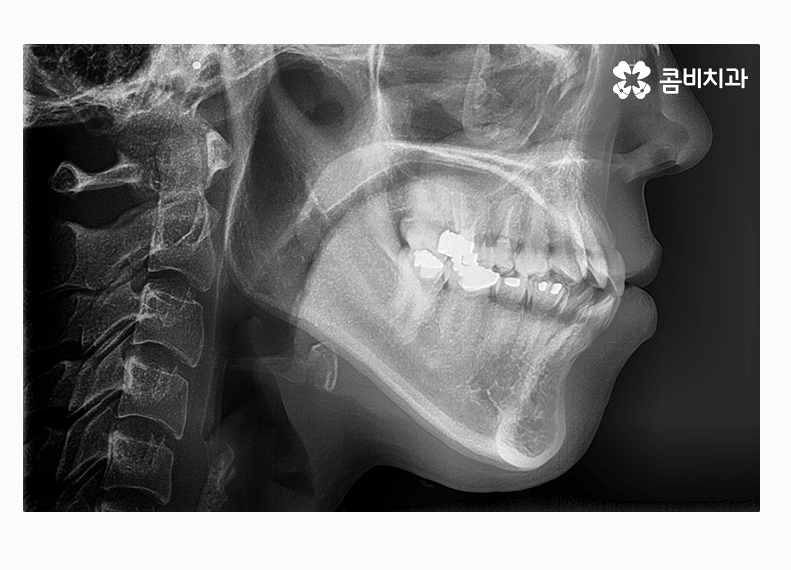

치아교정은 이처럼 단편적인 부분을 보고 치료 계획을

세우는 것이 아닌 3차원적으로 진단하고 얼굴과의

조화 역시도 중요하게 바라봐야 할 수 있어요.

부정교합 환자분의 경우 부정교합의 원인이 치아 혹은 골격적인

부분인지 정확한 파악을 먼저 해야 하며 비발치, 비수술적인

방법으로 치료가 진행될 수도 있고 반대로 발치와 수술이 함께

병행될 수 있으니 치료 과정은 개인차가 있다고 볼 수 있는데요.